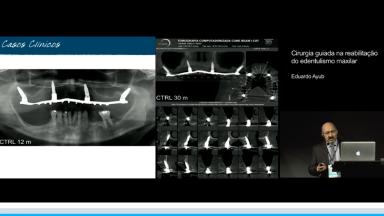

Esta conferência discute a cirurgia guiada assistida por computador, em maxila totalmente edêntula. As guias cirúrgicas são desenhadas e impressas a partir do planejamento cirúrgico em ambiente virtual, com a utilização de programas de software de planejamento que associam exames de tomografia computadorizada (CT) da anatomia óssea do paciente ao planejamento protético. Apresenta evidências científicas sobre a vantagens clinícas e acuracidade na transferência do posicionamento do implante guiado em comparação com a instalação de implantes a mão livre. Concluindo que, por meio da sistematização do planejamento, junto a procedimentos cirúrgicos guiados, é possível otimizar a cirurgia, minimizar complicações e oferecer mais conforto para o paciente.